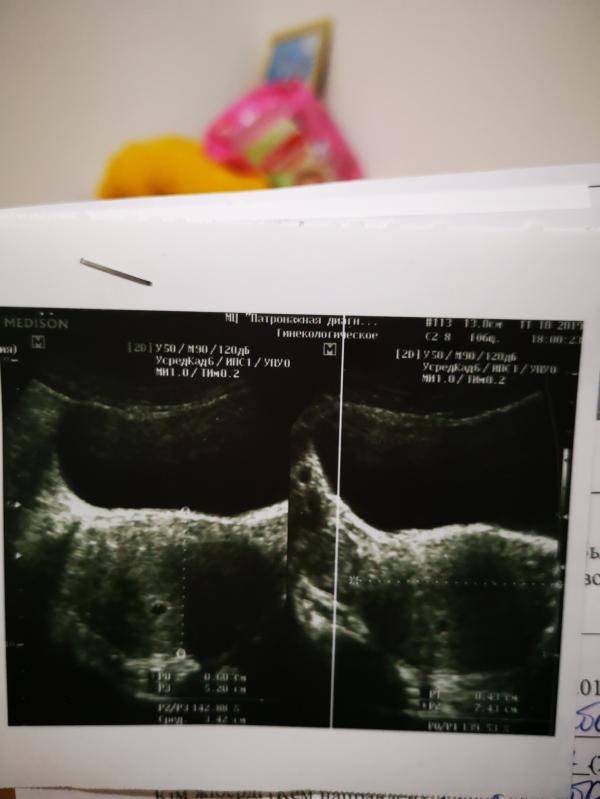

Узистка так и написала в описании, но сказала, что не уверена, но может быть двойня.

@ummannisa5 @nbvxx @erka там два снимка матки. Не уверена, но кажется сверху с левой стороны прикриплен еще один, на втором снимке)

Да я так и увидела , на первом один, на втором три😂 наверху один и ещё два снизу

2 вижу на 2 картинке рядом хорошо видно